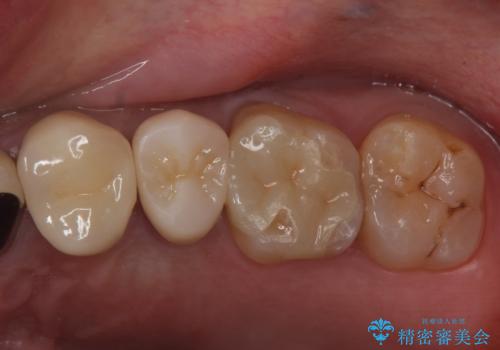

銀の詰め物をやりかえたい

- 銀の詰め物をやりかえたい。とのことで来院。

白い物を希望されたので、以下の提案を行い選んで頂いた。

①セラミックインレーにやりかえ

噛む面は白くなり、歯質を多く削らなくてすむが、

表面の黒いところまでは覆えない。

②ジルコニアクラウンで被せる

表面の黒いところまで覆う事ができる。

ただし、①よりも歯を大きく削ることになる。

患者様と相談し、黒いところも目立たなくしたいとのご希望だった。

そのため、歯質の削除量は増えるが、クラウンで被せる②の方針で行うことになった。